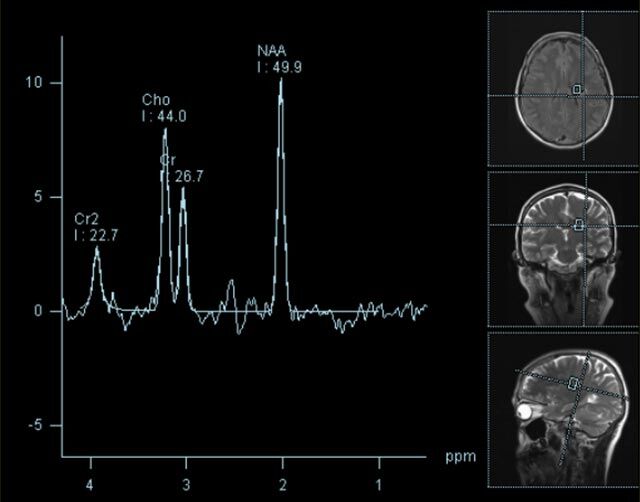

• Tumore, ggf. mit Spektroskopie

Spezialtechniken der Magnetresonanz

• MR-Spektroskopie

Diese Verfahren werden bei verschiedenen Fragestellungen in verschiedenen Körperregionen in die Messprotokolle sinnvoll eingefügt. Teilweise können dadurch Differenzierungenverschiedener krankhafter Prozesse verbessert werden.